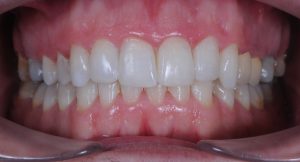

Maloclusión clase II

Se caracteriza por una relación anormal entre los dientes superiores e inferiores, donde los dientes superiores están demasiado adelantados en comparación con los inferiores.

Esto puede generar problemas funcionales, como dificultad para masticar, y también afectar la estética facial.

22 Semanas de Tratamiento